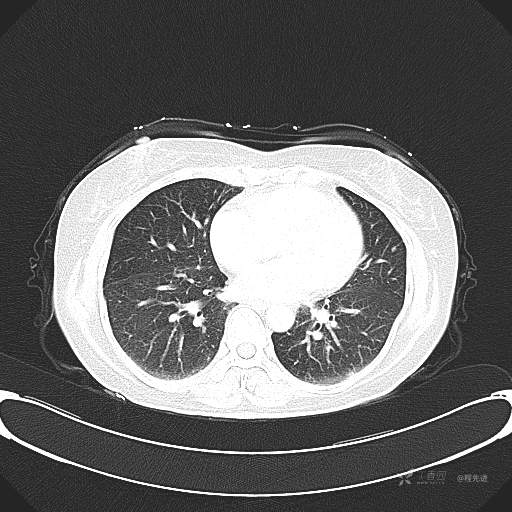

患者性别:女

患者年龄:57岁

简要病史:体检发现

CT增强

平扫CT值约40HU(未上传图像),增强后动脉期CT值约70HU,静脉期CT值约97HU。

肺硬化性血管瘤 (20)